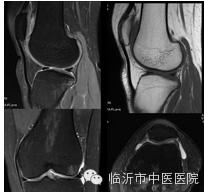

骨关节成像能更细致地视察膝关节半月板、韧带及滑囊的病变,做出准确的评估。

在早期关节软骨退变的诊断有一定的临床价值,可以提供客观、定量指标去检测骨性关节病的进展。